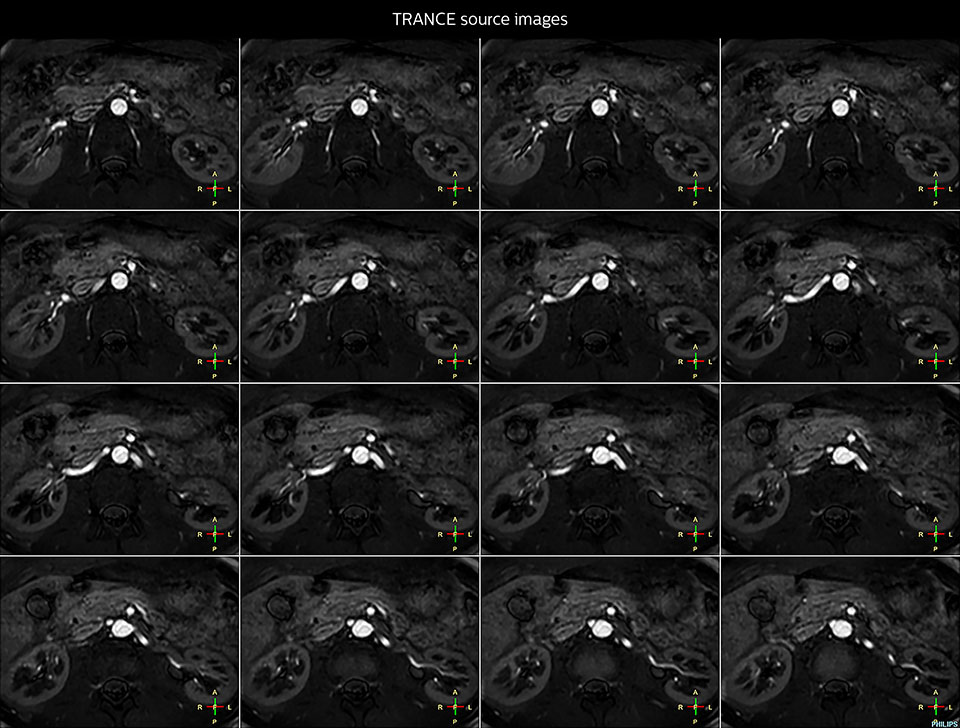

Non-contrast MRA of renal arteries

Imaging the renal arteries without contrast agent on Prodiva 1.5T.

TRANCE MIP

eMIP native Angio RL